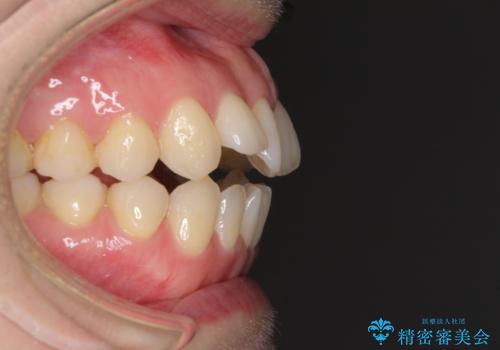

前歯の叢生とオープンバイト インビザラインでの矯正治療

- 前歯の開咬を気にして来院された患者様です。

開咬の治療は、前歯を閉じるように動かすとともに、上下臼歯を圧下(骨内にめり込ませる)させることで進めて行きます。

インビザラインは臼歯の圧下を効果的に行えるため、インビザラインを用いて矯正治療を行うこととしました。